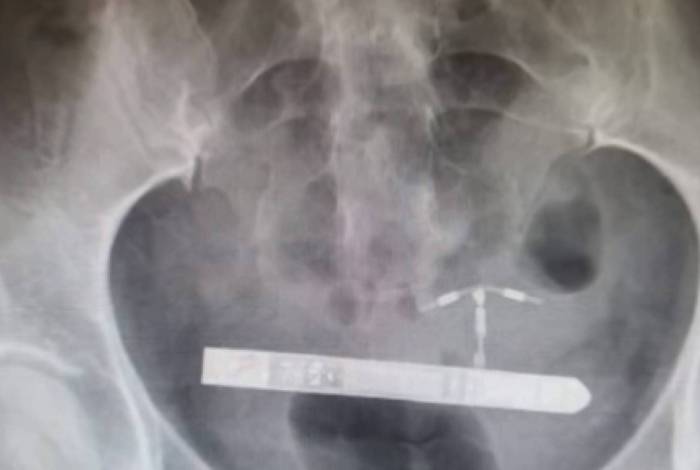

“Nós da equipe médica não conseguimos encontra-lo na vagina”, disse o ginecologista Greg Marchand. E logo, a mulher passou por um exame de raio x. “Fiquei surpreso quando percebi que ele estava na bexiga da paciente”.